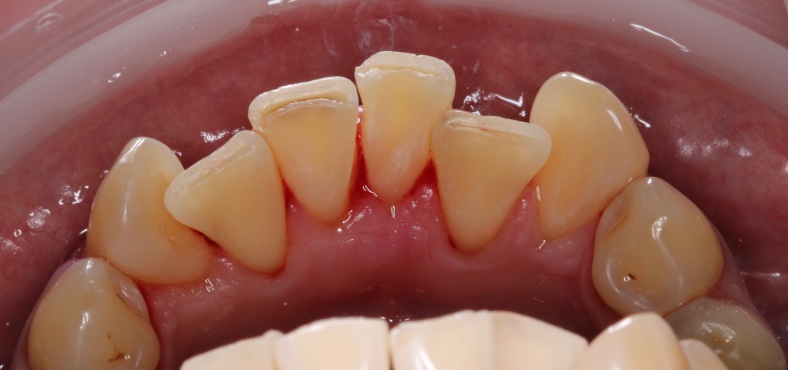

Наши работы

• Профессиональная гигиена